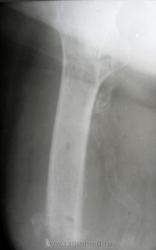

Помогите интерпретировать снимки. Женщине 73 года, в августе 2010 ампутация по поводу гангрены стопы, сахарный диабет. Около недели гнойное отделяемое из рубца, со слов.

В приёмном отделении, местный статус: отёка культи нет; свищ в области постеоперационного рубца, на момент осмотра отделяемого нет; гиперемии кожи культи нет.

Осмотр хирурга гнойного отделения: состояние удовлетворительное. В области п/о рубца участок гипергрануляции 0.5х0.5 см, отёка культи нет. Рубец - без признаков воспаления.

Поступила сегодня, результатов анализов еще нет. Поставила остеомиелит, но у меня впечатление, что на спил одет какой-то колпачок, но я ни разу такого не видела. Может, кому встречалось подобное?

Остеомиелит дистального конца культи.

ничего не имею против остеомиелита. Я его и поставила. Мне не ясен четкий, как по линеечке, ровный нижний контур и треугольная плотная тень с ровными контурами по наружному краю. Применяется ли какой-то колпачок на спил? Потому что у меня сомнение, что на самом дистальном краю - именно костная ткань...

Читаем Рейнберга: "Наиболее типичными для культи являются так называемые венечные, коронарные секвестры (рис. 115). Венечный остеонекроз имеет вид кольца или в более редких случаях - довольно высокого цилиндра. Он охватывает то всю кость по окружности, то только часть диафизарного цилиндра. Иногда венечный остеонекроз имеет форму воронки, образующейся из внутренних или внешних слоев коркового вещества."

Можете посмотреть http://v-ugnivenko.narod.ru/Rh/2-4.html - один в один

Коллега, или я чего-нибудь не понял или ошибка вкралась, но вы писали, что была ампутация стопы, а видим культю бедра(?)...

"...в августе 2010 ампутация на уровне средней трети бедра по поводу гангрены стопы, сахарный диабет" - пропустила в начале ветки.